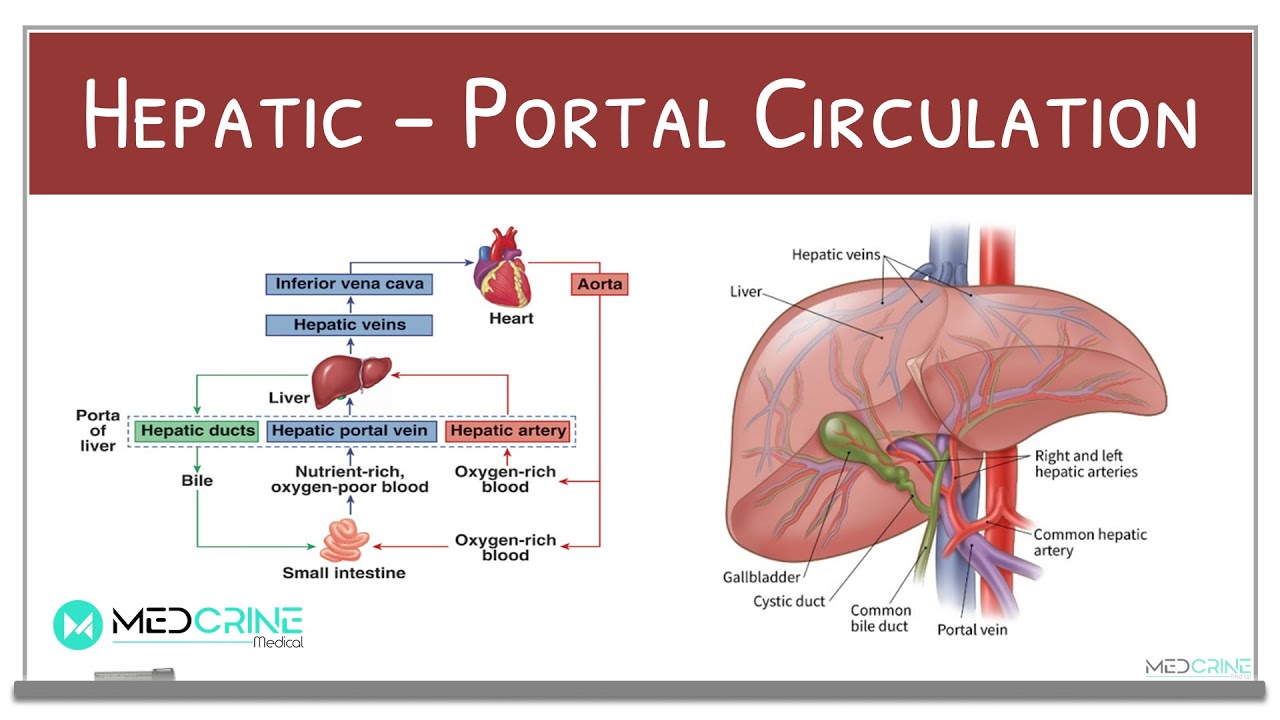

Hepatic Portal Circulation Physiology Explained YouTube

A P Hepatic Portal Circulation Diagram Quizlet